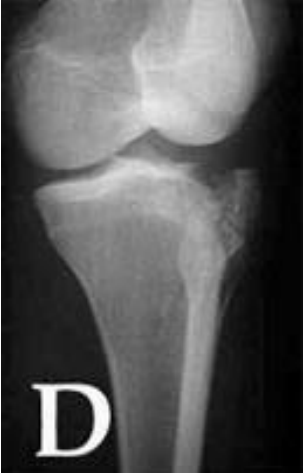

Observe a projeção radiográfica para fratura tibial superior, a seguir:

É CORRETO afirmar que é uma tomada em: